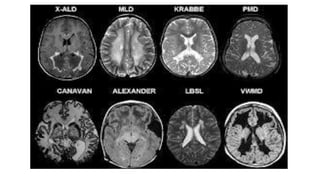

TIGROID SKIN/LEOPARD SKIN APPEARANCE

• Seen in Metachromatic Leukodystrophy, Pelizaeus Merzbacher disease

Van der Knaap disease

• T1- hypo, T2 and FLAIR- hyper

• bilateral subcortical cysts of CSF intensity affecting the anterior

ALEXANDER X-linked ALD

MLD

JUVENILE NCL VWMD

CEREBROTENDINOUS

XANTHOMATOSIS

duplication of LMNB1

DIFFUSE

ALEXANDER X-linked ALD KEARNS-SAYRE SYNDROME(C MLD JUVENILE NCL VWMD CEREBROTENDINOUS XANTHOMATOSIS duplication of LMNB1 DIFFUSE MILD